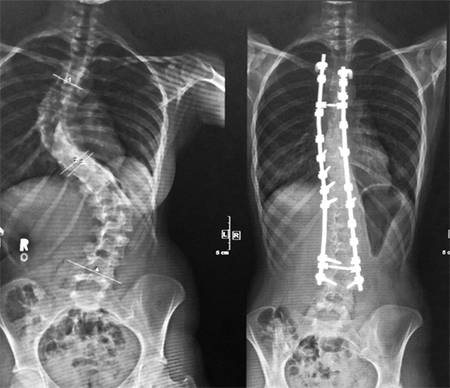

Before and after radiograph of a patient with scoliosis following traditional spinal fusion surgery.

Patients with curves over 50° are considered for surgery. Spinal fusion surgery has undergone numerous changes since its inception. Traditional surgery can last upwards of ten hours and recovery takes around two months. This can severely interrupt the active lives of young patients.  In recent years, the scoliosis community has witnessed an increase in the variety of surgical methods available, most notably Vertebral Body Tethering and Apifix (Israel). I understand that these new surgical interventions shorten recovery time and permit mobility.